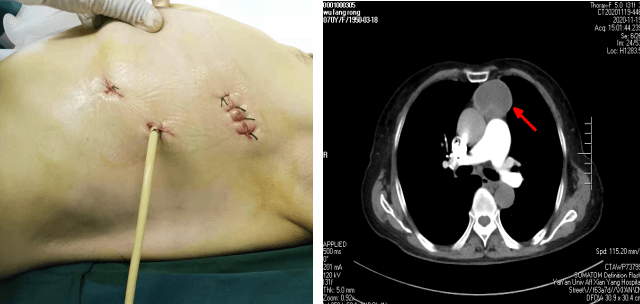

患者××,女,70歲,因“間斷腹部不適2月,加重10天” 于11月23日收入腫瘤/胸外科。胸部CT示前縱膈腫瘤。苗滿園主任帶領(lǐng)團(tuán)隊(duì)對(duì)該患者情況進(jìn)行了仔細(xì)的研究討論:縱膈腫瘤大小約10cm×6cm×6cm,邊界尚清,內(nèi)有鈣化,考慮良性腫瘤可能性大。與家屬溝通后選擇胸腔鏡下手術(shù)。手術(shù)團(tuán)隊(duì)經(jīng)精心術(shù)前準(zhǔn)備,于11月25日為患者實(shí)施全麻下“胸腔鏡下縱膈腫瘤切除術(shù)”。術(shù)中發(fā)現(xiàn)腫瘤起于心臟左前上方,經(jīng)主動(dòng)脈弓前達(dá)胸腔頂。術(shù)中仔細(xì)分離,克服因心臟跳動(dòng)及主動(dòng)脈搏動(dòng)的不穩(wěn)定性,保護(hù)好心臟、膈神經(jīng)、主動(dòng)脈,出血量少,手術(shù)十分順利,歷時(shí)1小時(shí),完整切除腫瘤。嚴(yán)格按圍手術(shù)期ERAS管道管理改進(jìn)措施,選用留置導(dǎo)尿管單根引流,避免傳統(tǒng)手術(shù)因引流管粗硬導(dǎo)致的術(shù)后疼痛不適,術(shù)后當(dāng)天即可獨(dú)立下床活動(dòng),生活完全自理。患者及家屬非常滿意,極大地提高了患者的就醫(yī)體驗(yàn)。